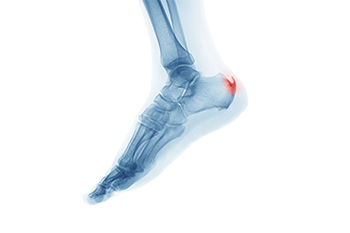

Heel spurs are formed by calcium deposits on the back of the foot where the heel is. This can also be caused by small fragments of bone breaking off one section of the foot, attaching onto the back of the foot. Heel spurs can also be bone growth on the back of the foot and may grow in the direction of the arch of the foot.